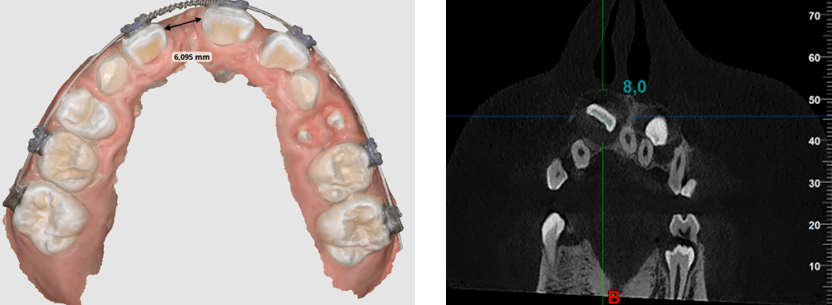

El plan de tratamiento consistió en retirar la ortodoncia fija anterior y cementar brackets con técnica 4x2 filosofía Roth 0,022 con una secuencia de arcos 0.014 niti termoactivado, 0.018niti termoactivado previo a procedimiento quirúrgico. Se requieren 8 mm (espacio requerido) para el incisivo central 1.1 y se tenía un espacio inicial de 6,09 (espacio disponible) (Fig 9 y 10), para control radiográfico inicial se realizó una radiografía periapical con técnica de bisectriz (Fig 11)

Fig 9 y 10. Espacio disponible y espacio requerido

Fig 11. Rx periapical con técnica de bisectriz